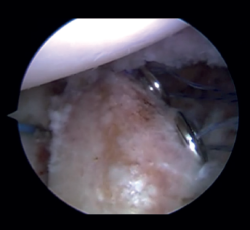

Arthroscope is introduced through the anterosuperior portal, and the glenoid guide is introduced through the posterior portal, and passed paralel to the glenoid surface until the hook is located at the centre of the bone defect. The guide is secured with two cannulas inserted through two small accessory incisions, until connecting with the posterior cortical layer. Both cortical layers are drilled through them using a 2.8 mm drill fitted with a sheath so that on withdrawing the drill the sheath is positioned at drilling level. This step is made twice to introduce two sheaths: one above and the other below the glenoid guide hook and spaced 10 mm apart. Through these sheaths we advance two monofilament loops that are retrieved sequentially through the anterior portal for subsequent passing of the graft. At this point we can remove both sheaths and the glenoid guide, taking care to prevent the guide hook from coming into contact with the glenoid surface in order to avoid damaging to the cartilage.

Figure 3. View from the anterosuperior portal (left shoulder). Monofilaments inserted through the sheaths from posterior to anterior for subsequent passing of the threads that will introduce the graft.